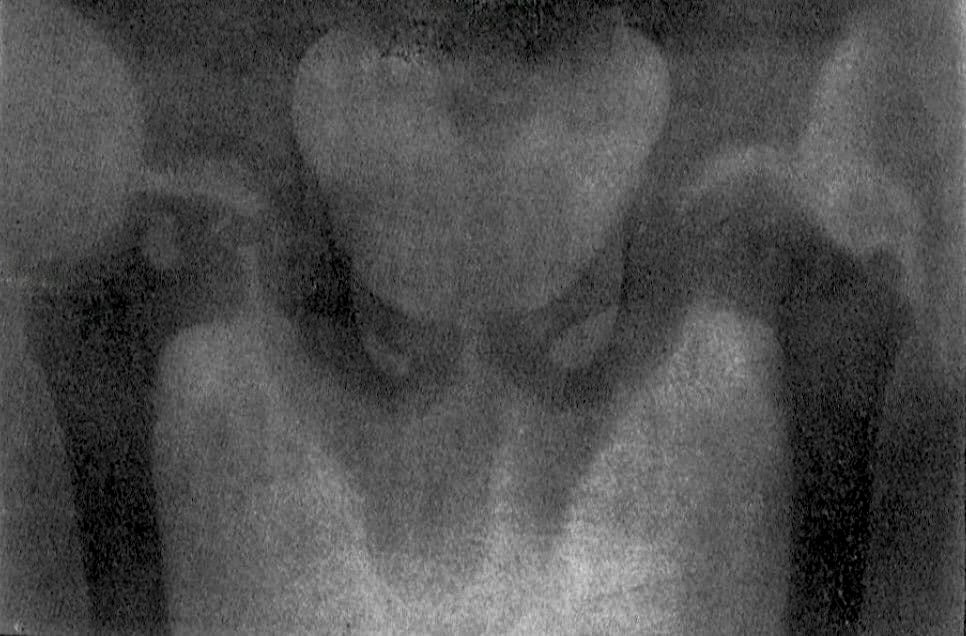

Legg–Calvé–Perthes disease (LCPD) is an idiopathic avascular necrosis of the proximal femoral epiphysis in children. It typically presents insidiously, sometimes after minor trauma, with hip pain, limp, or restricted movement. It most often affects boys aged 4–10 years, is unilateral in 90% of cases, and when bilateral, the hips are usually affected sequentially rather than simultaneously.

In 1910, Legg described cases of juvenile hip disease in children at Boston Children’s Hospital, characterised by limp, restricted movement, and radiographic flattening of the femoral head.

He emphasised the process as distinct from tuberculosis, arguing that the condition represented a unique disorder of the proximal femoral epiphysis. His observations were published almost simultaneously with those of Jacques Calvé in France and Georg Perthes in Germany, giving rise to the eponym Legg–Calvé–Perthes disease.

The Roentgenogram showed a flattened head and a distinct necrotic area just outside the epiphyseal line in the neck, with apparently some thickening of the neck…